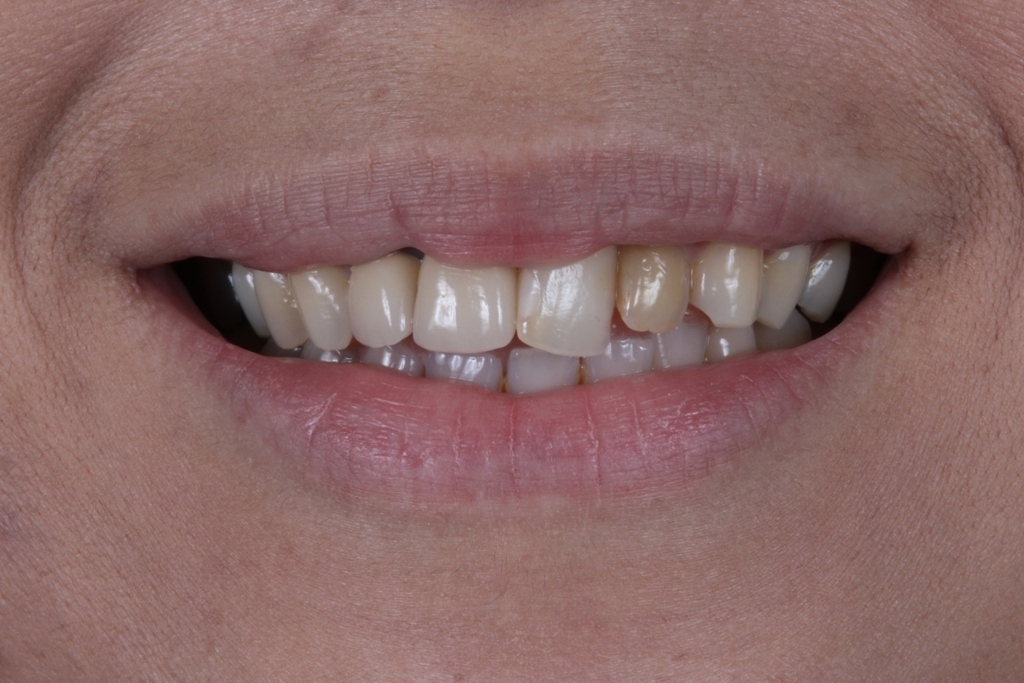

LENTES DE CONTATO DENTAIS EM PORCELANA

A.M.I.D.